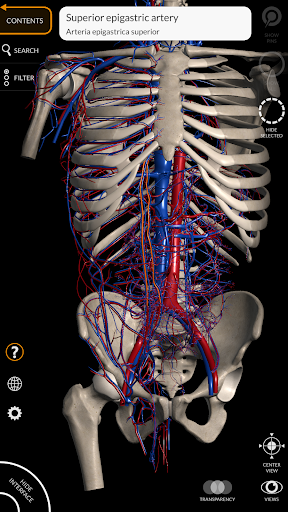

يتيح لك "Anatomy 3D Atlas" دراسة التشريح البشري بطريقة سهلة وتفاعلية.

من خلال واجهة بسيطة وبديهية، من الممكن ملاحظة كل بنية تشريحية من أي زاوية.

تتميز النماذج التشريحية ثلاثية الأبعاد بتفاصيل خاصة ودقة تصل إلى 4K.

يسهل التقسيم حسب المناطق والمناظر المحددة مسبقًا مراقبة ودراسة الأجزاء الفردية أو مجموعات الأنظمة والعلاقات بين الأعضاء المختلفة.

• الجهاز القلبي الوعائي

• من خلال تحديد نموذج أو دبوس، يظهر المصطلح التشريحي ذي الصلة